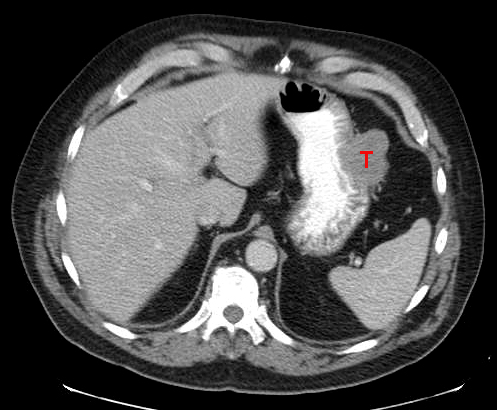

Η καλύτερη διαγνωστική εξέταση είναι η ενδοσκόπηση του ανώτερου πεπτικού, με λήψη βιοψιών για αποκλεισμό κακοήθειας.Θα πρέπει πάντα να γίνεται έλεγχος για ελικοβακτηρίδια του πυλωρου.

Η αιμορραγία από πεπτικό έλκος έχει θνητότητα 5-10%.Συνήθως αντιμετωπίζεται ενδοσκοπικά .

Η διάτρηση συνήθως αντιμετωπίζεται χειρουργικά ,συρραφή και επιπλοοπλαστικη του διατρηθεντος έλκους.

Η πυλωρικη στένωση συνήθως αντιμετωπίζεται ενδοσκοπικά.